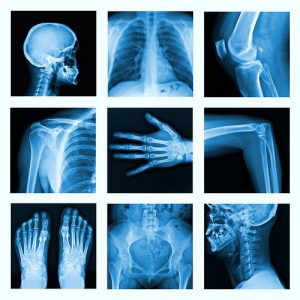

O Raio-X Digital na Z2 é uma ferramenta indispensável para o suporte em diversas áreas críticas da saúde:

- Ortopedia e Traumatologia: Essencial para diagnósticos precisos de fraturas, luxações e doenças degenerativas ósseas.

- Saúde Pulmonar: Investigação minuciosa de pneumonias, derrames pleurais, nódulos e outras patologias do trato respiratório.

- Acompanhamento Pós-operatório: Monitoramento da consolidação óssea e posicionamento de implantes com clareza milimétrica.